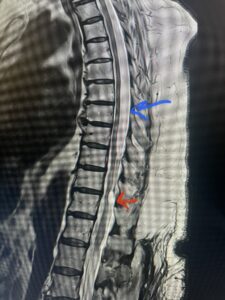

Fig. 1 Sagittal T2-weighted thoracic MRI demonstrating both T10-11 focal intradural arachnoid cyst (red arrow) and larger upper thoracic cyst that appears to extend from T4-T8 (blue arrow).

Fig. 1b Axial T2-weighted thoracic MRI demonstrating spinal cord compression from T10-11 arachnoid cyst (red arrow)

Fig. 1c Axial T2- weighted thoracic MRI demonstrating spinal cord compression with severe anterior displacement of the spinal cord from upper thoracic arachnoid cyst.

This 67-year-old female presents with progressive heaviness and numbness of the legs and difficulty ambulating. Her right leg was worse than her left. She had right greater than left hip flexor weakness. She was hyperreflexia in her lower extremities. An MRI (Fig. 1) demonstrated an intradural arachnoid cyst at T10-11 with severe spinal cord compression. She also appeared to have an arachnoid cyst above from T4-T8 with anterior displacement and compression of the spinal cord. Because of her severe myelopathy and the findings on MRI the patient underwent laminectomy for surgical decompression of cyst. Intraoperatively the focal arachnoid cyst at T10-11 appeared as a small bubble crushing the spinal cord anteriorly with scarring of the arachnoid with no CSF flow above or below.

The cyst was fenestrated and immediately CSF flow was reestablished. We performed a laminectomy at T6-7 for the upper cyst region which was observed to be more consistent with normal anatomy. We fenestrated the arachnoid. It was felt that the upper level was a secondary phenomenon as a result of CSF flow blockage. Post operatively she had an uneventful course with return of normal strength although she had some residual numbness.